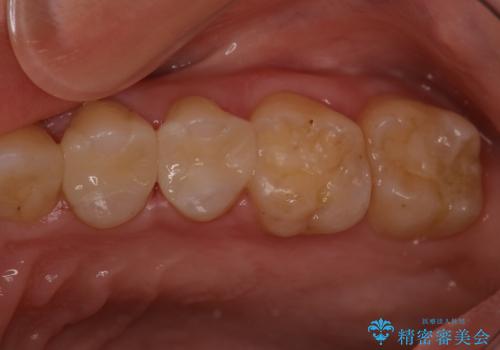

定期検診で虫歯発見。セラミック治療

- 定期検診に通われている患者様で虫歯を発見し患者様に話をしたら、治療を進めていきたいとのことだったので治療を行いました。

まずは虫歯をしっかりと取る事が大切です。

虫歯をとった後は、削った形に型を取る事で隙間なく歯にあった被せ物ができてきます。